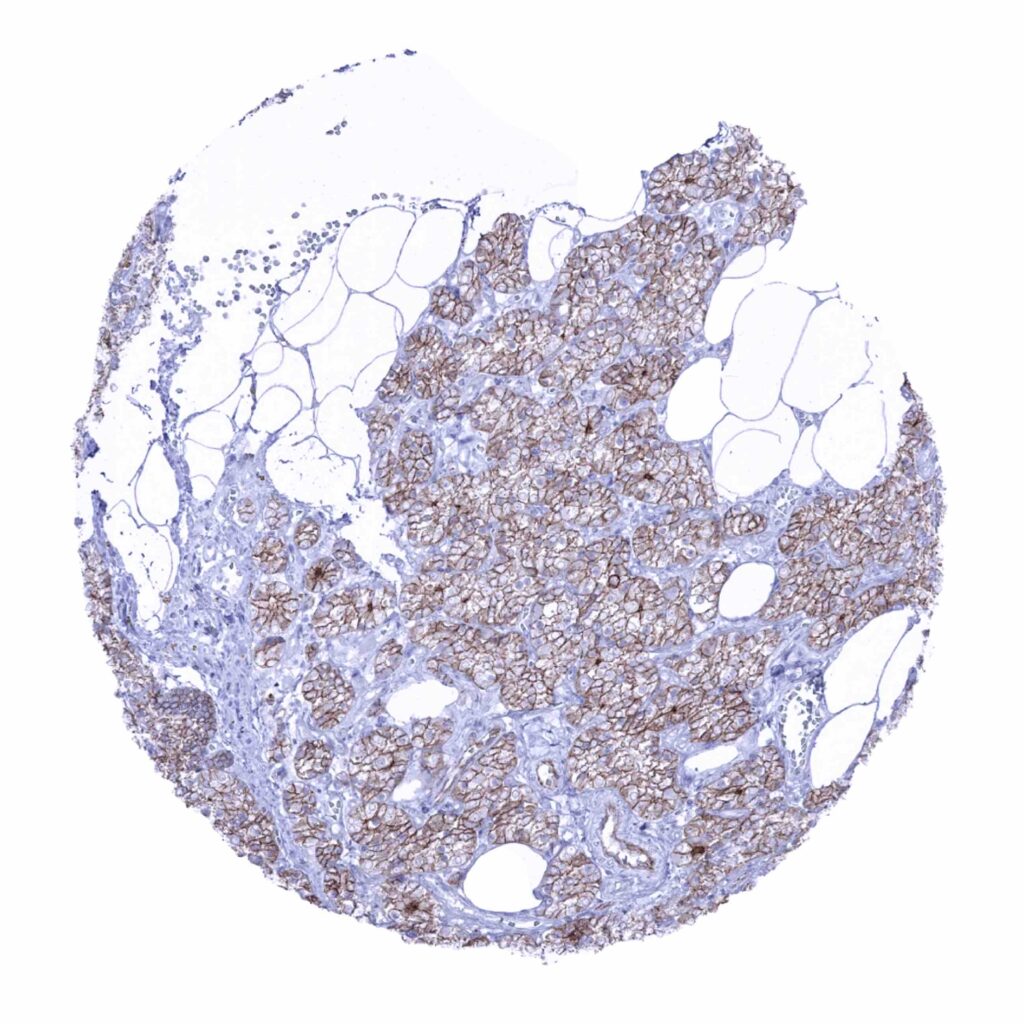

Breast – Luminal cells show a moderate membranous occludin immunostaining while basal lack staining (occludin immunohistochemistry)